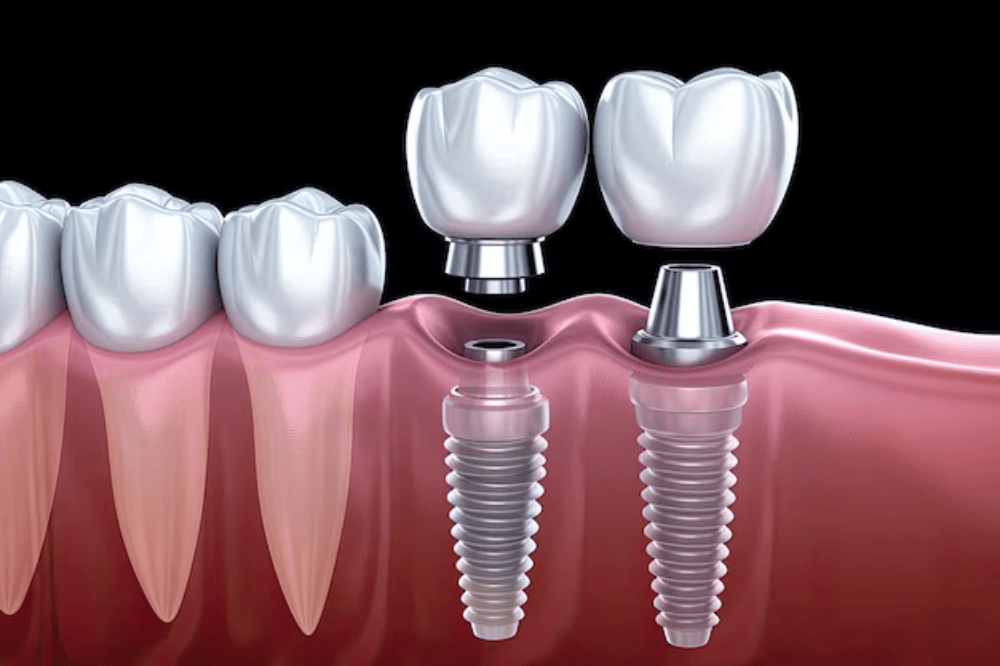

A dental implant is a small titanium post that is placed into the jawbone to act as an artificial tooth root. Once the implant fuses with the bone, a custom-made crown is placed on top to look and function like a natural tooth.

Consultation & 3D X-rays / CT Scan

Personalized Treatment Planning

Implant Placement Surgery

Healing & Bone Fusion (3–6 months)

Crown or Bridge Attachment